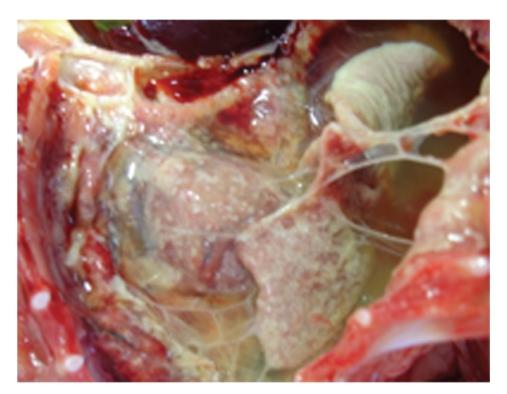

Feline coronaviruses (FCoVs) are found throughout the world. Infection with FCoV can result in a diverse range of signs from clinically inapparent infections to a highly fatal disease called feline infectious peritonitis (FIP). FIP is one of the most serious viral diseases of cats. While there is neither an effective vaccine, nor a curative treatment for FIP, a diagnostic protocol for FCoV would greatly assist in the management and control of the virus. Clinical findings in FIP are non-specific and not helpful in making a differential diagnosis. Haematological and biochemical abnormalities in FIP cases are also non-specific. The currently available serological tests have low specificity and sensitivity for detection of active infection and cross-react with FCoV strains of low pathogenicity, the feline enteric coronaviruses (FECV). Reverse transcriptase polymerase chain reaction (RT-PCR) has been used to detect FCoV and is rapid and sensitive, but results must be interpreted in the context of clinical findings. At present, a definitive diagnosis of FIP can be established only by histopathological examination of biopsies. This paper describes and compares diagnostic methods for FCoVs and includes a brief account of the virus biology, epidemiology, and pathogenesis.

猫冠状病毒(FCoVs)在全球范围内均有发现。感染FCoV可导致从临床无明显症状感染到一种名为猫传染性腹膜炎(FIP)的高度致命疾病等一系列不同症状。FIP是猫最严重的病毒性疾病之一。虽然既没有有效的疫苗,也没有针对FIP的治愈性治疗方法,但FCoV的诊断方案将极大地有助于该病毒的管理和控制。FIP的临床症状不具有特异性,对鉴别诊断没有帮助。FIP病例中的血液学和生化异常也不具有特异性。目前可用的血清学检测对检测活动性感染的特异性和敏感性较低,且与低致病性的FCoV毒株即猫肠道冠状病毒(FECV)发生交叉反应。逆转录聚合酶链反应(RT-PCR)已用于检测FCoV,且快速灵敏,但结果必须结合临床症状进行解读。目前,只有通过活检组织的组织病理学检查才能确诊FIP。本文描述并比较了FCoVs的诊断方法,并简要介绍了该病毒的生物学、流行病学和发病机制。